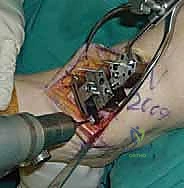

4. وضع أدلة القطع (Jig Placement and Alignment)

تعتمد دقة الجراحة على المحاذاة الصحيحة. يتم استخدام أجهزة توجيه متطورة (Jigs) تثبت على عظمة الساق باستخدام دبابيس معدنية. يتم التحقق من صحة الزوايا والمحاور باستخدام جهاز الأشعة السينية المباشر داخل غرفة العمليات (C-arm Fluoroscopy). يضمن الدكتور هطيف أن يكون القطع موازياً للأرض تماماً عند وقوف المريض.

تتكون غرسة STAR من ثلاثة أجزاء رئيسية ولا تستخدم الأسمنت العظمي (Cementless)، بل تعتمد على النمو العظمي الدقيق داخل مسام الغرسة لتثبيتها بشكل دائم:

- المكون الظنبوبي (Tibial Component): صفيحة معدنية مسطحة من سبائك الكوبالت والكروم (Cobalt-Chromium)، تُثبت في أسفل عظمة الساق (الظنبوب) بواسطة أسطوانتين معدنيتين تدخلان في العظم لضمان الثبات المطلق.

- المكون الكاحلي (Talar Component): قطعة معدنية تغطي قبة عظم الكاحل، مصممة بشكل تشريحي منحني يحاكي تماماً شكل العظمة الأصلية، وتحتوي على أخدود طولي.

- الحشوة البلاستيكية المتحركة (Mobile Polyethylene Bearing): هذا هو سر نجاح غرسة STAR. هي قطعة من البلاستيك الطبي عالي الكثافة (UHMWPE) توضع بين القطعتين المعدنيتين. هذه القطعة ليست ثابتة، بل تنزلق بحرية للأمام والخلف، وتسمح بدرجة طفيفة من الدوران. هذا التصميم "المتحرك" يقلل بشكل هائل من إجهاد القص (Shear Stress) على واجهة العظم والمعدن، مما يقلل من احتمالية تخلخل الغرسة (Loosening) على المدى الطويل، ويمنح المريض نطاق حركة فسيولوجي مذهل.